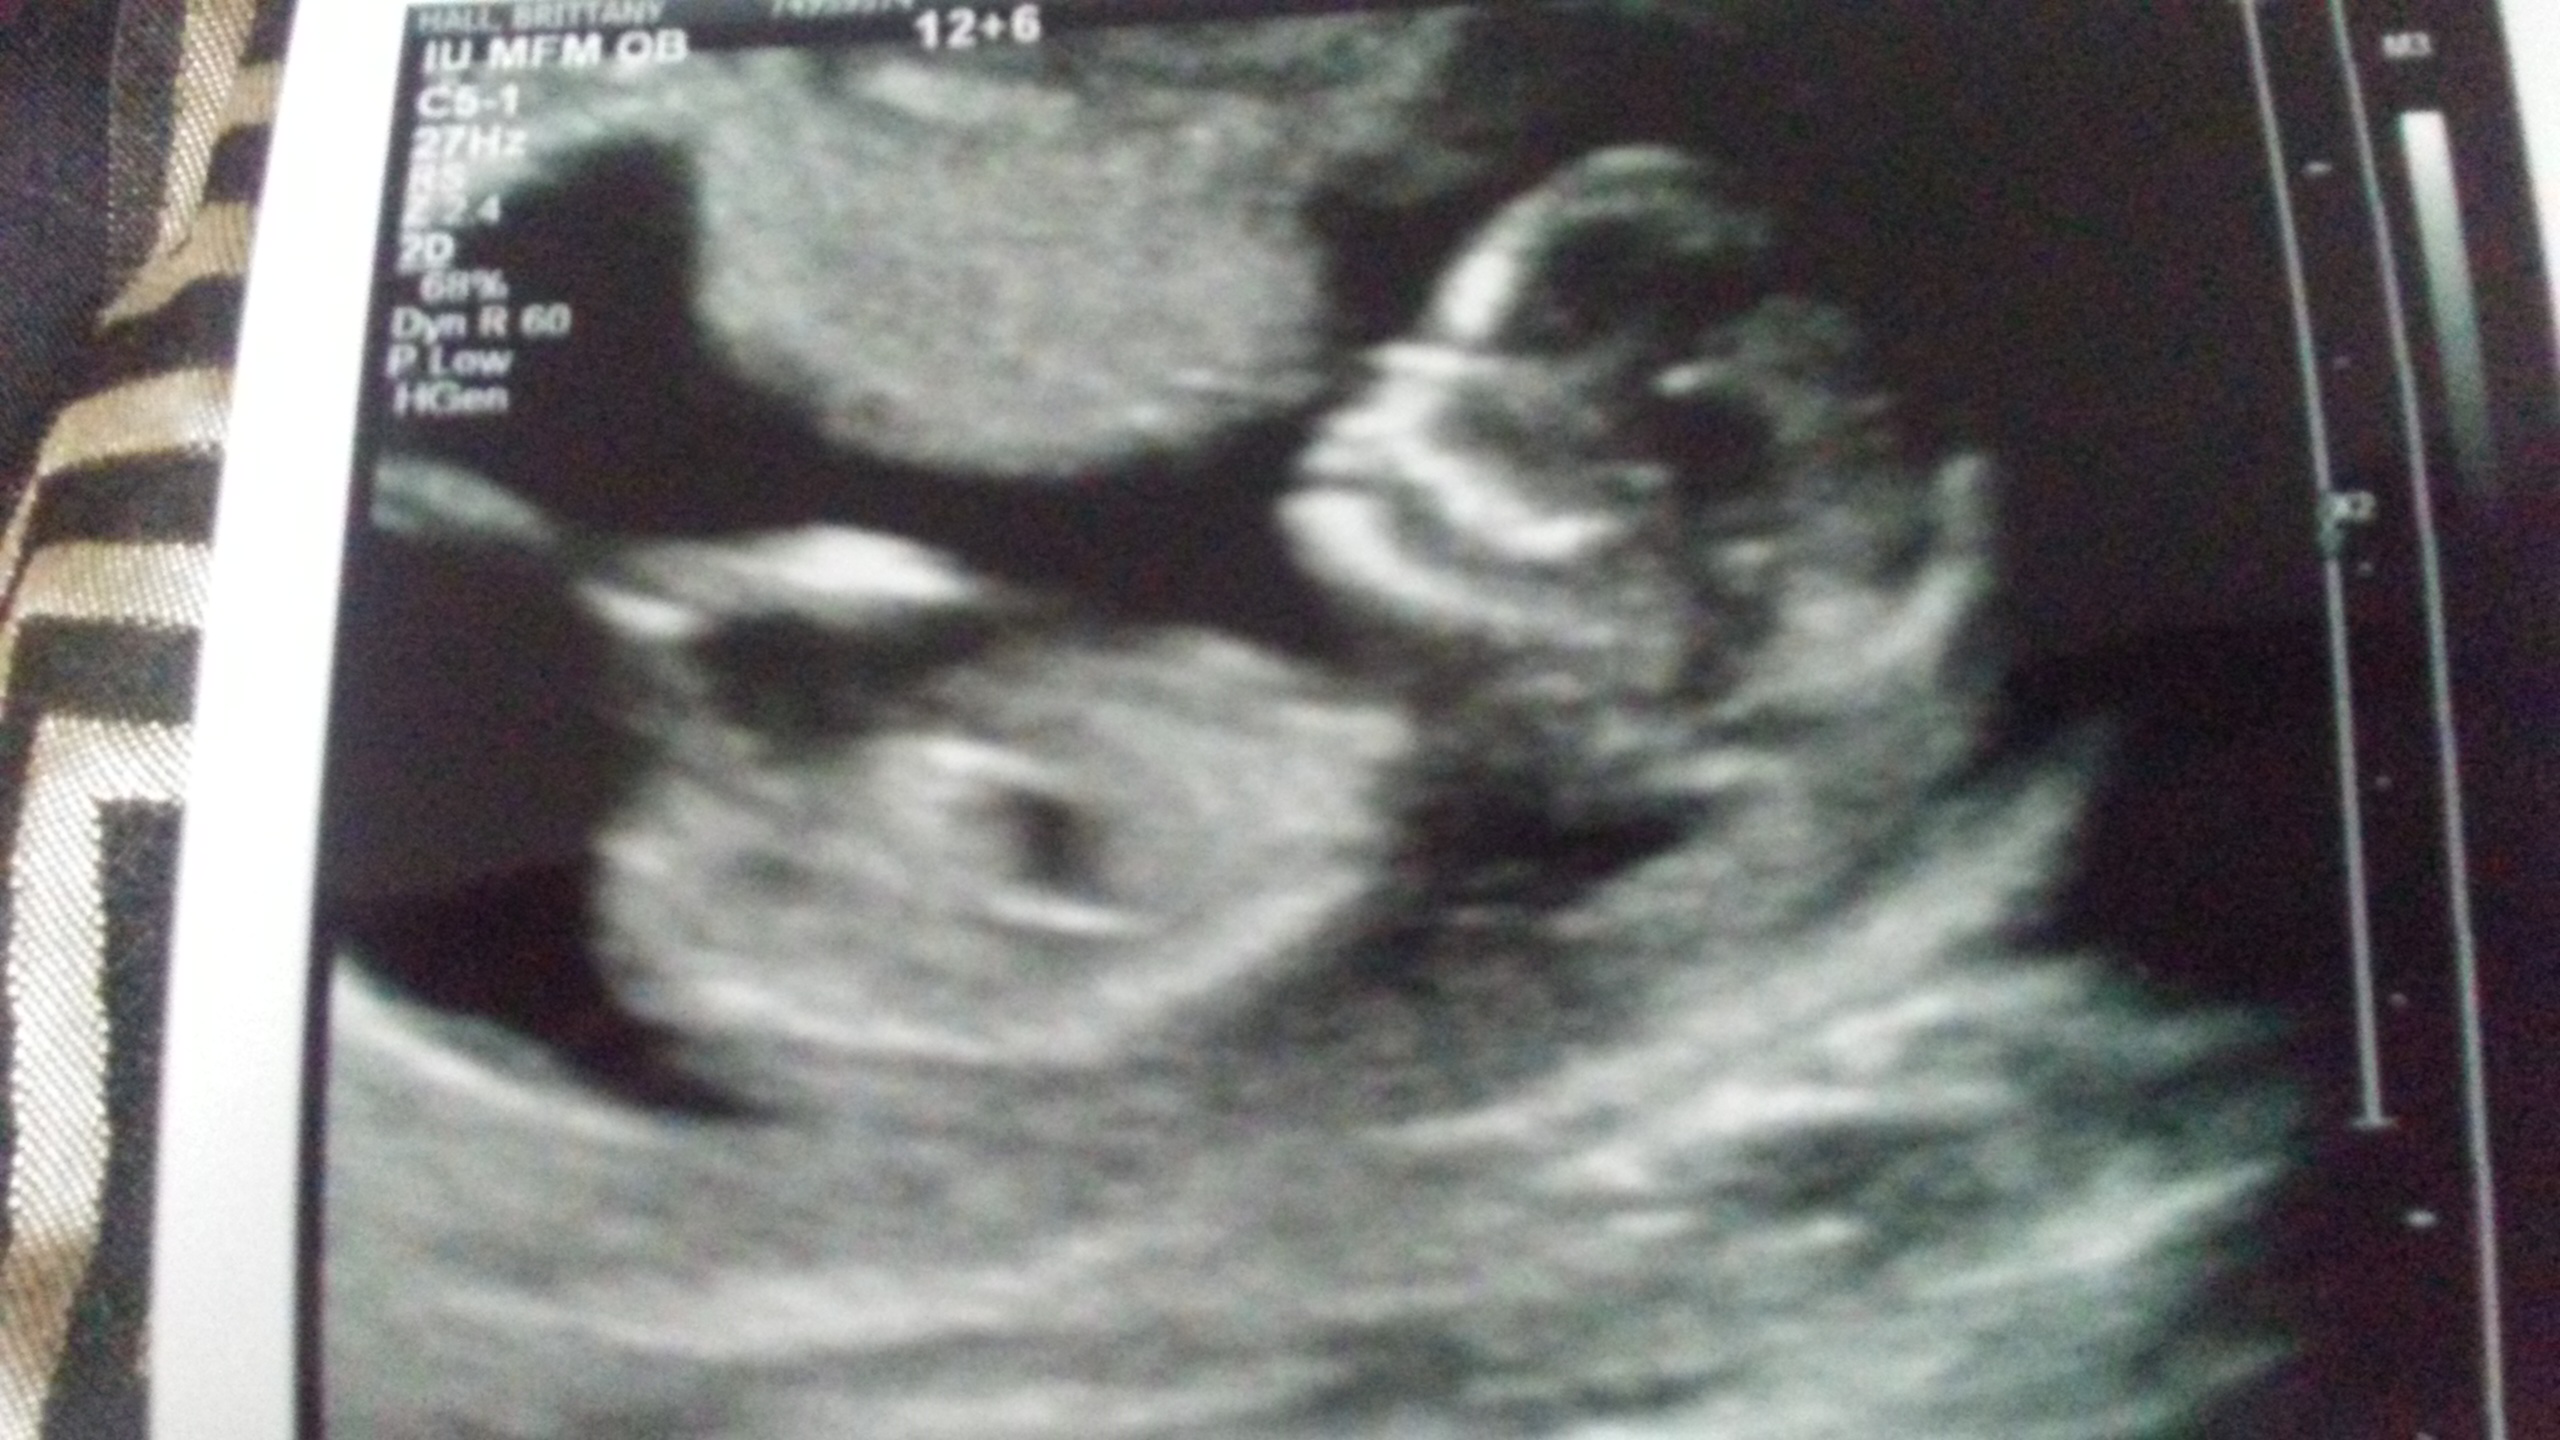

Baby is measuring 13 weeks 2 days... Attachment 32852 Attachment 32853Attachment 32854